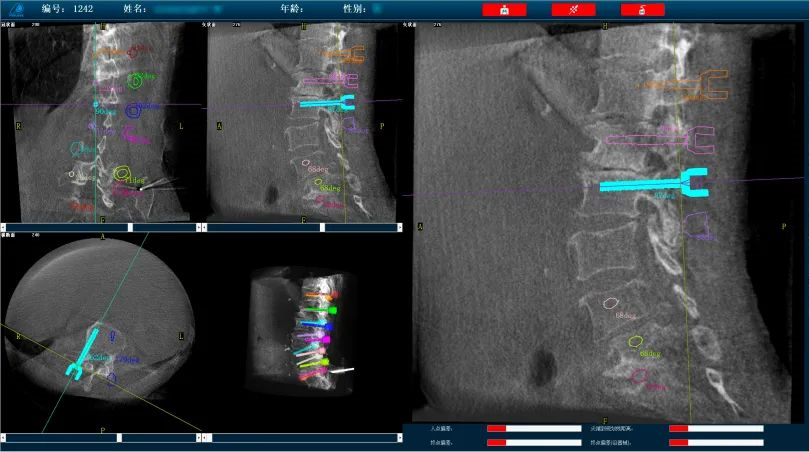

而外科手術機器人與三維C形臂配合,基于3D影像數(shù)據(jù),利用手術規(guī)劃軟件,術前模擬植入物狀態(tài),引導醫(yī)生進行預手術規(guī)劃,輔助評估和及時調整手術路徑規(guī)劃設計,機械臂準確運動到規(guī)劃位置,借助導向套筒,為醫(yī)生提供穩(wěn)定的導針置入路徑。外科手術機器人以實現(xiàn)準確、微創(chuàng)手術為首要目標,通過手術機器人準確定位可以減小患者手術過程中的開口大小,減少神經(jīng)損傷風險,實現(xiàn)手術操作的準確度和安全性。

普愛醫(yī)療骨科手術機器人可廣泛地應用于多節(jié)段脊柱外科手術,輔助醫(yī)生定位病灶部位,為脊柱外科手術(經(jīng)皮椎體成形術、椎弓根螺釘內固定術等術式))提供術前手術流程規(guī)劃、入釘位置、角度可視化引導,模擬仿真入釘輔助。產(chǎn)品優(yōu)勢特點如下:

外科手術機器人配備高精度光學追蹤系統(tǒng)和機械臂,可基于3D影像數(shù)據(jù),利用手術規(guī)劃軟件,引導醫(yī)生進行預手術規(guī)劃,輔助準確定位植入物或手術器械,精度可達亞毫米級。尤其對高風險、復雜程度高的手術具有明顯優(yōu)勢,可有效降低手術風險。

操作流程簡單化:多次手動入釘定位,操作繁瑣,骨科手術機器人可以實現(xiàn)多枚螺釘路徑一次性規(guī)劃,節(jié)省規(guī)劃定位時間,簡化手術操作流程,提高置釘效率。

復雜手術標準化:直觀的軟件操作界面引導,減少手術中的不確定環(huán)節(jié),使得復雜手術流程標準化,讓從業(yè)經(jīng)驗不足的醫(yī)生也能快速掌握,縮短醫(yī)生的學習曲線。